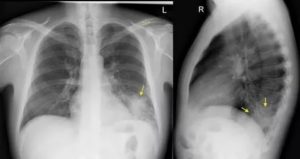

Флюорографическое исследование – основной метод диагностики пневмонии. Проводится врачом-рентгенологом или рентген-лаборантом с дальнейшей расшифровкой. Алгоритм проведения флюорографии:

- Проводится снимок в прямой проекции (пациент прижимается грудью к датчику).

- Далее в боковой проекции (больной заводит руку за голову и прижимается к прибору боковой стороной грудной клетки).

- Снимки проводятся при спокойном дыхании и на высоте вдоха, с задержкой дыхания.

После проведения снимков их необходимо проявить. В некоторых кабинетах используется цифровой формат флюорографии. Когда снимки проявлены, врач приступает к их расшифровке.

Флюорографию нужно делать тогда, когда присутствуют симптомы болезни. Если у человека выявлено крупозное или очаговое заболевание, вторичные рентгенограммы назначаются для наблюдения перемен «плохих» теней при излечении.

Выявить особенности крупозного воспаления возможно на рентгенограмме. Однако при патологии медицинским стандартом диагностики считается рентгенография в двух проекциях (прямая и боковая). Такого рода список процедур совершают для оценки численности пораженных частей легких и исследования состояния средостения.

По этой причине, чтобы получить максимум информации о состоянии органа и оценить развитие пневмонии рентген принято делать в двух проекциях (передней и боковой). В попытках повысить результативность исследования, делают снимок в косой или диагональной проекции. Однако, подобное практикуется редко.

При сегментарной форме происходит поражение целого сегмента легкого. При этом пораженный участок исключается из процессов газообмена, что приводит к серьезным затруднениям дыхательного процесса. На иллюстрации ниже изображена правосторонняя сегментарная пневмония.

Еще одним неоспоримым плюсом рентгенографии является тот факт, что снимок делается в двух проекциях. Это позволяет обнаружить патологические изменения, которые могут быть не видны только в прямой проекции.

Крупозная пневмония легче всего выявляется при рентгенологическом исследовании. Тем не менее для постановки точного диагноза врачи предпочитают делать рентгеновские снимки в двух проекциях. Это дает им возможность определить число пораженных воспалением сегментов органа и определить состояние средостения.